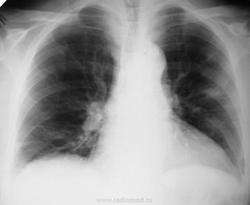

Мужчине 53 года. Госпитализирован в инфекционное отделение с диагнозом: "Лихорадка неясного генеза". Болен 5-й день, 38-39 температура. Снимок обзорный за 16.06 и 2 проекции+томограммы за 27.06. По первому снимку (приемное отделение, заказан обзорный, увидела утром) описала инфильтрацию нижнего легочного поля справа и... плотные старые очаги

. Что скажете коллеги? КТ не работает.

Какая, все-таки, неточная наука, рентгенология. Я бы, по снимку от 17.06. написал бы не инфильтрацию в нижней доле справа, а очаговый процесс (верятнее всего, пневмонию) в верхней доле левого легкого. На снимках от 27.06. отметил бы нарастание процесса, распространение и на верхюю долю правого легкого, заключение: двусторонняя очаговая пневмония, прогрессирующее течение болезни. Обследование на ТВС, конечно же не повредит, но туберкулез обычно так быстро не прогрессирует. А септические эмболы, должны уже были распасться.

Спасибо за комментарии! Перефотографировала, эти картинки мне нравятся больше. Мокроты просто нет, кашля нет.

Мда, томограммы стали определеннее, и на первый план начали выходить объемные образования. Пневмония становится менее вероятной, возрастают шансы метастатического процесса, что не исключает лабораторного обследования на ТВС. У Dr.Drug в прошлом году был случай с лихорадкой и гематогенным распространением, над которым все голову сломали, на секции вроде МТС из тонкой кишки. Кстати, вариант метастазирования первым предложил Валентин Львович.

Менингит. Золотистый стафилококк высеяли в ликворе. Так что второе исследование трактую как септические эмболы. Для полного счастья жду на контроль, обратное развитие увидеть. Центральный распад на некоторых очагах разглядеть можно. Есть и шанс мтс, но невелик.